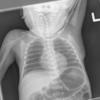

Normal neonate

Date: 02/07/2010

Views: 5844